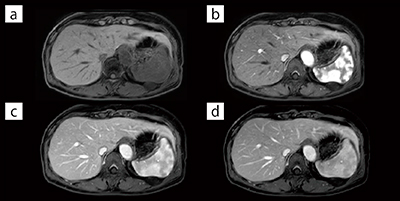

(2) 肝細胞特異性造影剤Gd-EOB-DTPAの肝細胞造影相は,通常息止めによる“eTHRIVE”(脂肪抑制併用T1WI turbo field echo法)にて撮像しているが,患者の状態により呼吸停止が困難な場合もある。そこで,新たに撮像可能となったFFE-MV XD法を使用することにより,自由呼吸下でT1WI FFE撮像を可能とした(図3)。これにより,呼吸停止困難な患者であっても,診断に耐えられる肝細胞相画像取得を可能とした。

図3 自由呼吸下T1WI-MV XD FFEの画像

肝臓Gd-EOB-DTPA MRI検査における肝細胞相の自由呼吸下T1WI-MV XD FFE画像である。自由呼吸下撮像において呼吸運動による画質劣化を十分に低減可能である。

(画像ご提供:王子総合病院様)